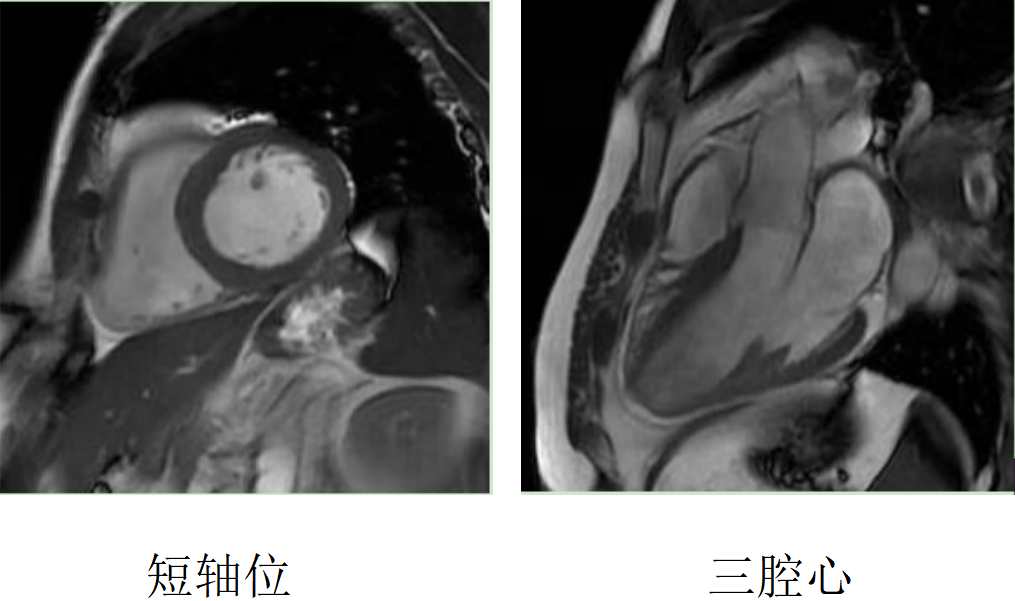

心臟磁共振被稱為心臟“一站式”檢查,通過(guò)多參數(shù)成像能夠?qū)π呐K的結(jié)構(gòu)、功能、室壁運(yùn)動(dòng)、心臟瓣膜、心肌灌注和活性進(jìn)行“一站式”評(píng)估。主要通過(guò)電影序列(短軸、兩腔心、四腔心、三腔心)、T2WI序列、首過(guò)灌注序列以及延遲強(qiáng)化序列對(duì)心臟進(jìn)行綜合成像。

右冠狀動(dòng)脈供血區(qū)透壁心梗伴心肌纖化

擴(kuò)張型心肌病

肥厚型心肌病,舒張末期心尖形似“黑桃A征”